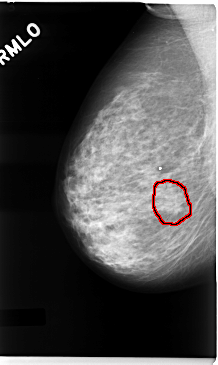

C_0041_1.RIGHT_MLO

RIGHT_MLO LINES 4736 PIXELS_PER_LINE 2824 BITS_PER_PIXEL 12 RESOLUTION 50 OVERLAY

FILE: C_0041_1.RIGHT_MLO.OVERLAY

TOTAL_ABNORMALITIES 1

ABNORMALITY 1

LESION_TYPE MASS SHAPE IRREGULAR MARGINS SPICULATED

ASSESSMENT 4

SUBTLETY 3

PATHOLOGY MALIGNANT

TOTAL_OUTLINES 1

BOUNDARY